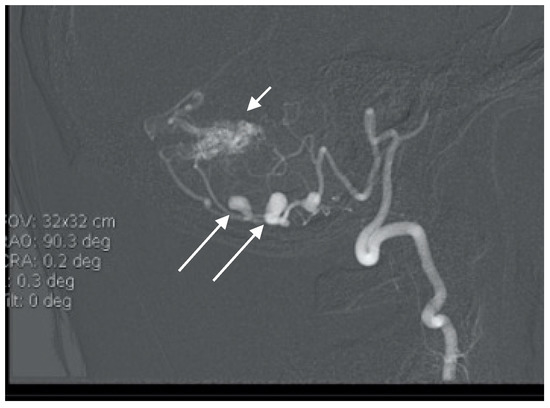

Figure 1. Angiogram misdiagnosed as aneurysm of bifurcation of the basilar artery (BA) in case report 1.

A 57-year-old female hypertonic patient was admitted to the neurology unit of a regional hospital in a mild Hunt and Hess grade for sudden-onset headache and vomiting. Computed tomography (CT) confirmed Fischer grade 2 subarachnoid hemorrhage (SAH). Following atypical angiography findings, an aneurysm on the bifurcation of the basilar artery (BA) was suspected (Figure 1), and the patient was urgently referred for endovascular treatment. Following catheter placement and 3 Dimensional—Digital Subtraction Angiography imaging, an aneurysm on the peripheral branch of the SCA was found, which was inaccessible for endovascular treatment due to the luminal diameter of the vessel. An additional MRI confirmed the suspected location and gigantic size of the partially thrombosed lesion, and the patient was prepared for surgery. With a midline supracerebellar approach, trapping of the parent artery and extirpation of a large (15 × 18 mm) thrombosed sac with preservation of the precentral vein were performed. Histological findings were without surprise; no mycotic agents or bacterial inflammation in the aneurysmal wall were revealed. Her postoperative course was uneventful, and follow-ups are undertaken every year.